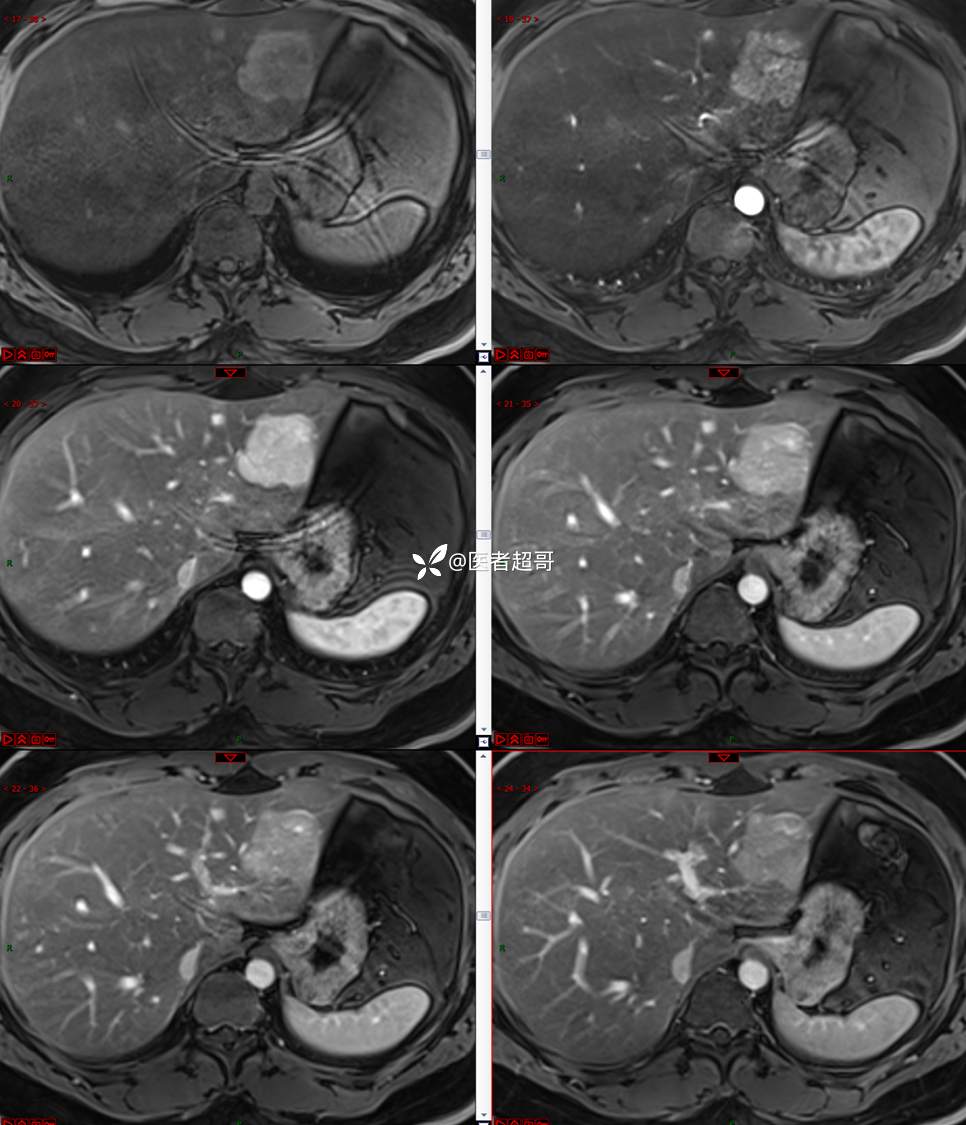

【影诊笔记800】青年男性,肝脏占位,特殊对比剂提示富血供,您能想到啥?有结果!

现病史:患者缘于5天前体检时发现肝占位性病变,未予以特殊处置。现患者为求系统诊治就诊于我院,行普美显提示:肝左叶富血供占位,请结合临床及其他检查,肝多发血管瘤,脂肪肝,肝囊肿,请结合临床。门诊以“肝占位性病变”收入我科。病程中,饮食睡眠可,二便可,近期体重未见明显变化。